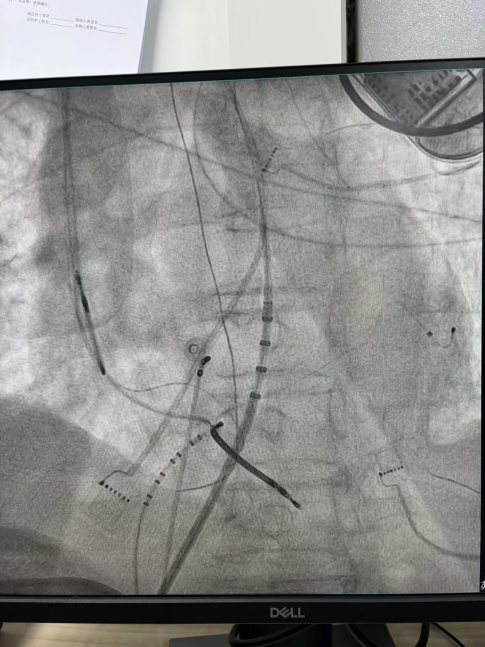

右心室后组乳头肌室早电位

王林林主任医师谨慎操作,成功进入心外膜达到病变位置。术中,患者反复自发多形态室速,且转为室扑,同时出现血流动力学不稳定,需多次电除颤方能终止发作,标测难度极大。这就要求医疗团队必须在有限的标测时间内精准定位室速消融靶点,并结合心内外膜基质特征制定消融策略。经针对性消融后,患者未再自发室速,且室性早搏转为单一形态,经判定为右心室乳头肌来源,随即予以一并消融。术后经心室程序电刺激验证,室速未再被诱发。

术后,患者恢复良好,接受持续心电监测7天,整个住院期间未再发生室速,心悸症状也得以缓解。对于ICD术后反复室速放电的患者而言,射频消融术是减少室速发作、减轻痛苦的一项有效手段。